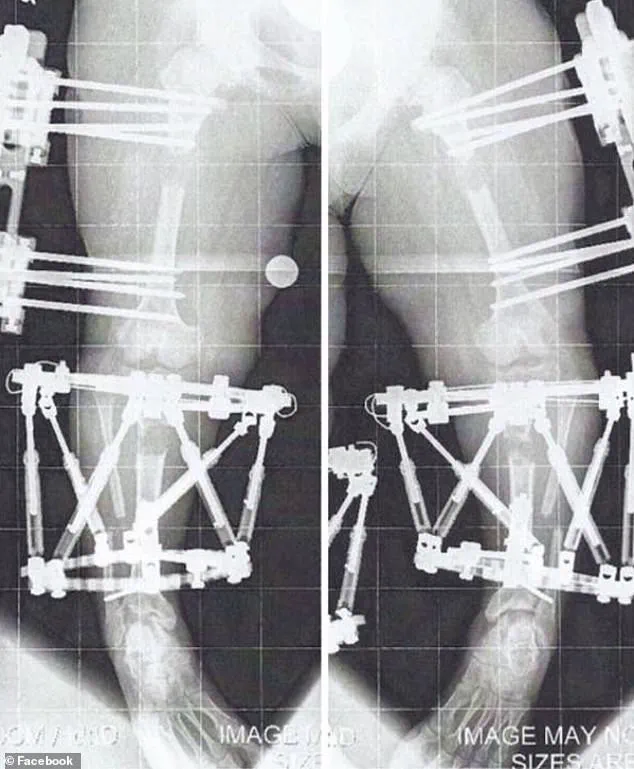

The procedure, which involves extending bones by approximately 1 millimeter per day during the ‘distraction phase,’ is a testament to both medical innovation and the relentless pursuit of physical normalcy.

As new bone forms in the gap created by the surgical break, patients endure a grueling process that can span months, often described as ‘months of twists and turns’ with ‘a little blood, sweat, and tears.’ This is the reality for individuals like Crews, whose journey through multiple limb-lengthening procedures has become a case study in resilience and medical necessity.

After the desired length is achieved, the device—whether an external fixator or internal rod—is removed, and the new bone is left to fuse back together.

This healing phase is critical; without proper integration, the results of the surgery can be compromised.

The initial post-surgery recovery from Crews’ first procedure was grueling.

It involved two to three hours of personal training sessions five days a week, along with daily exercises and stretches, all done in her own time.

By the time the fixators were removed from her first leg in April 2011, the physical and emotional toll was immense.

She recalled the period after removal as one month of no weight-bearing, followed by a painstaking re-learning of how to walk.

Using a walker for two weeks, then quad canes for another, she eventually transitioned to unassisted walking by June.

This journey, while arduous, was a necessary step toward regaining independence and mobility.

Her arm lengthening procedure, which involved fixators implanted in January 2012 when she was 17, was less restrictive than her leg surgeries, as the fixators were limited to her humerus, allowing her to remain mobile during the process.